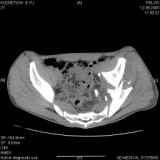

Уважаемые коллеги! Хотелось бы услышать совет по тактике лечения представлленого больного.Поступил после лечения в одном изотделений области. Травма 2,5 месяца назад. После выведенияиз шока был произведен остеосинтез перелома бедра, предплечья, до перевода к нам проводилосьвытяжение по оси шейки бедра за стержень, введенный в большой вертел. На сегодня деформацияригидна, клинически мобильности не определяется. Заранее признателен. P.S. Данный вид травм не включен в перечень "высокотехнологичных операций", направить длялечения по квотам Минздрава очень сложно.

Это обзорные и косые снимки

С уважением,

Привет, Леонид. Оскольчатый высокий двухколонный перелом в такие сроки трогать не надо, т.к. это про такие переломы сказано: "кто с ножом на Ж. пойдет тот в ней и останется...".